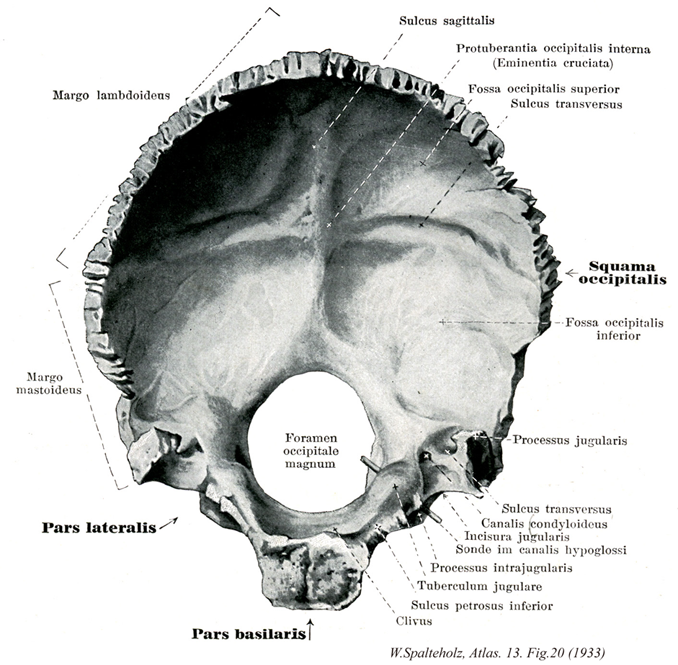

Spalteholz HANDATLAS DER ANATOMIE DES MENSCHEN VON WERNER SPALTEHOLZ

020

- 020_00【Occipital bone後頭骨 Os occipitale】 Bone located between the sphenoidal, temporal, and parietal bones.

→(脳頭蓋の後下部にある単一の骨で、頭蓋の脊柱上端に連なる部をつくる。前端に近く大きな大後頭孔があって、それより前方の底部、両側の外側部、後方の後頭鱗の3部に分けられる。前方は蝶形骨体、外方は側頭骨の岩様部、上方は頭頂骨と接するその形はほぼ舟状で、内面はくぼみ、外面はふくれる。後頭骨は胎生期後半には4つの部分に分離している。これらの4部が癒合して単一の骨になるのは生後3~4年たってからであるが、各部の名前だけは成人の骨にも残されている。)

- 020_01【Lateral part of occipital bone外側部(後頭骨の) Pars lateralis ossis occipitalis】 The part that is lateral to the foramen magnum.

- 020_02【Basilar part of occipital bone底部(後頭骨の) Pars basilaris (Os occipitale)】 The part that ascends from the foramen magnum to the spheno-occipital synchondrosis.

- 020_03【Squamous part of occipital bone後頭鱗(後頭骨の) Squama occipitalis】 The part that is posterior to the foramen magnum.

- 020_04【Lambdoid border of occipital boneラムダ縁;ラムダ状縁;人字縁(後頭骨の) Margo lambdoideus ossis occipitalis】 Articulates with the parietal bone.

- 020_05【Mastoid border of occipital bone乳突縁(後頭骨の) Margo mastoideus ossis occipitalis】 Margin of the occipital bone that articulates with the temporal bone.

- 020_06【Groove for superior sagittal sinus上矢状洞溝;矢状溝 Sulcus sinus sagittalis superioris; Sulcus sagittalis】 Shallow depression for the superior sagittal sinus.

- 020_07【Internal occipital protuberance内後頭隆起 Protuberantia occipitalis interna】 Projection on the internal surface opposite the external occipital protuberance. It forms the midpoint of the cruciform eminence.

- 020_07a【Cruciform eminence十字隆起 Eminentia cruciformis】 Bony projection in the shape of a cross with the internal occipital protuberance at its center.

- 020_08【Cerebral fossa; Fossa for occipital lobe of brain大脳窩;大脳後頭窩(後頭骨の) Fossa cerebralis; Fossa occipitalis cerebralis; Fossa occipitalis superior】 Depression that lodges the occipital lobes.

- 020_09【Groove for transverse sinus横洞溝;横溝 Sulcus sinus transversi; Sulcus transversus】

- 020_10【Cerebellar fossa; Fossa for cerebellum小脳窩;小脳後頭窩(後頭骨の) Fossa cerebellaris; Fossa occipitalis inferior】 Depression that lodges the cerebellum.

- 020_11【Jugular process of occipital bone頚静脈突起 Processus jugularis】 Projection located lateral to the jugular foramen that is visible internally and externally. It corresponds to the transverse process of a vertebra.

- 020_12【Condylar canal顆管 Canalis condylaris】 Passageway for transmission of a vein that begins at the sigmoid sinus and ends posterior to the occipital condyle.

- 020_13【Jugular notch of occipital bone頚静脈切痕(後頭骨の) Incisura jugularis ossis occipitalis】 Recess that, together with the petrous part of temporal bone, forms the jugular foramen.

- 020_14【Hypoglossal canal舌下神経管 Canalis nervi hypoglossi; Canalis hypoglossi】 Passageway that begins superolateral to the foramen magnum and ends anterolateral to the occipital condyle. It transmits CN XII and a venous plexus.

- 020_15【Intrajugular process頚静脈孔内突起;孔内突起 Processus intrajugularis】 Process that occasionally divides the jugular foramen into a lateral compartment for the passage of the internal jugular vein and a medial compartment for the transmission of nerves.

- 020_16【Jugular tubercle頚静脈結節 Tuberculum jugulare】 Small protuberance above the hypoglossal canal.

- 020_17【Groove for inferior petrosal sinus下錐体洞溝;錐体溝 Sulcus sinus petrosi inferioris; Sulcus petrosus】

- 020_18Blumenbach, Clivus of【Clivus of basilar part of occipital bone斜台(後頭骨底部の) Clivus】

- 020_19【Foramen magnum大後頭孔;大孔 Foramen magnum; Foramen occipitale magnum】 Large opening in the occipital bone for the medulla oblongata. vessels, and nerves.